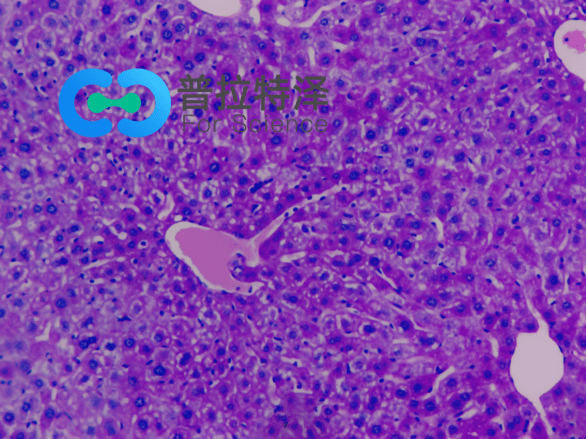

PAS染色法,全稱為過碘酸-雪夫染色法(Periodic Acid-Schiff stain)。在組織學(xué)上,主要用來檢測組織中的糖類。它利用過碘酸將糖類相鄰的兩個碳上的羥基氧化成醛基,再與Schiff試劑中的無色品紅結(jié)合,形成紅色物質(zhì),從而顯示糖原和其他多糖物質(zhì)在細胞內(nèi)的分布。

普拉特澤生物承接PAS染色染色等病理染色相關(guān)服務(wù)上萬例,積累了操作大量經(jīng)驗,為大家詳細分享PAS染色染色的實驗操作步驟和實驗是需的材料,同時為廣大科研工作者開展線上的理論培訓(xùn)與線下實操,可承接染色實驗外包服務(wù)